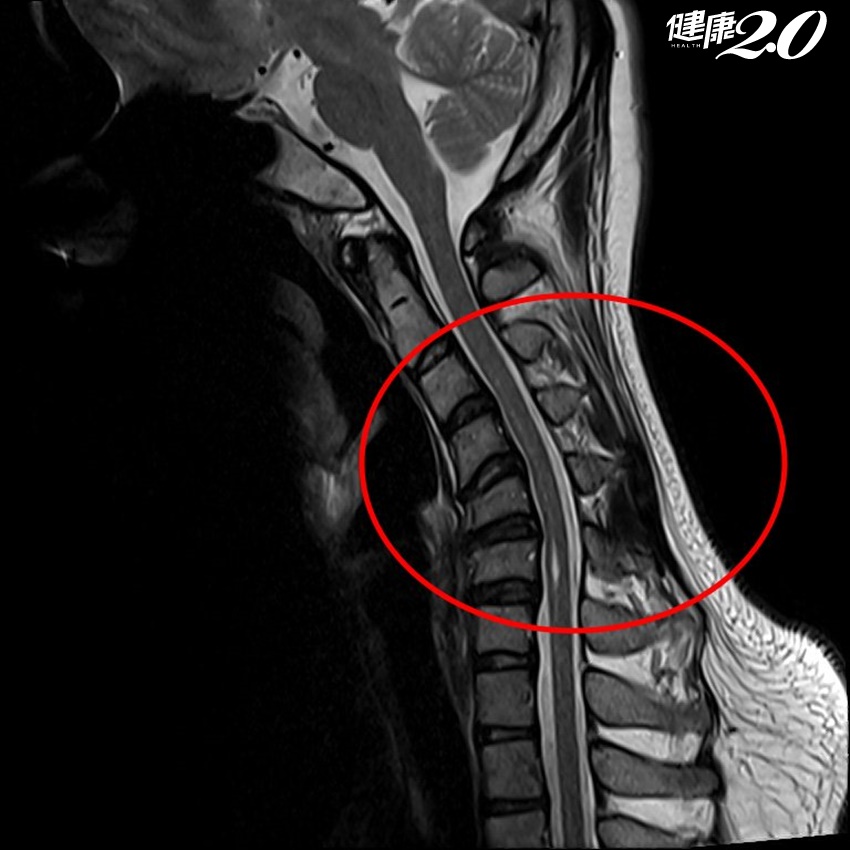

林志隆解釋,小紫因長年姿勢不當,頸椎長期承受壓力,經核磁共振檢查後,發現已經出現脊髓空洞症的前兆,脊髓內滲入不少液體,幸好發現得早,空洞的情況相當輕微,評估後無須開刀引流,但後續除了改正姿勢,也要定期追蹤觀察空洞的發展情形。

▲電腦斷層顯示脊髓內滲入不少液體。(亞大醫院提供)